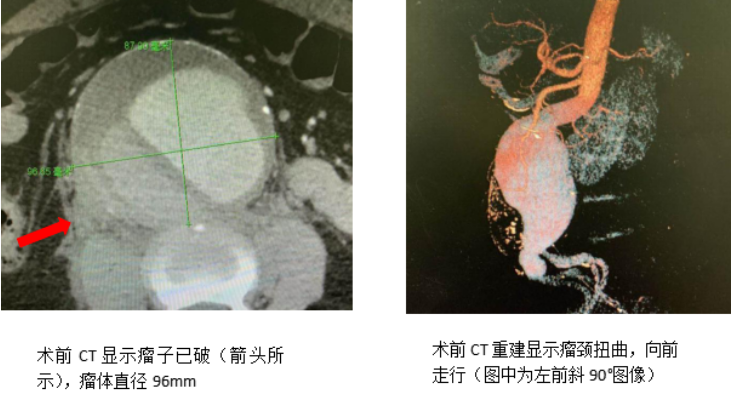

菏泽市立医院心血管外科团队成功抢救破裂性腹主动脉瘤一例

84岁李先生突然感到腹部疼痛难忍,腹部ct平扫显示腹主动脉瘤破裂